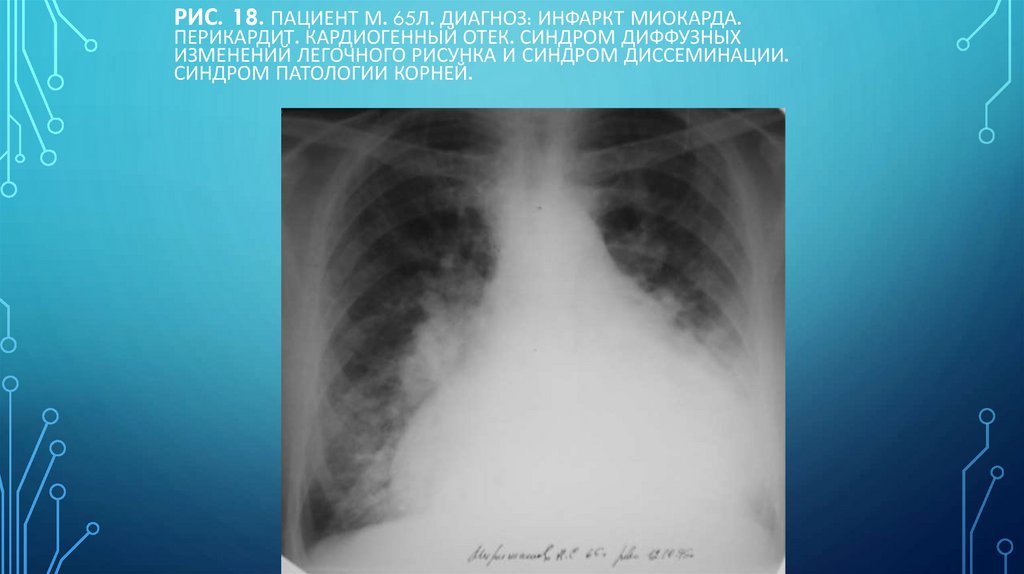

• Рис.11б. Рентгенограмма органов

грудной полости в прямой проекции.

Отрицательная динамика: массивный

смешанный (интерстициальный и

альвеолярный) отек преимущественно

медиальных отделов легких - симптом

«крыльев бабочки». Трапециевидная

форма сердечной тени, вызванная

экссудативным перикардитом.

109. Рис. 18. Пациент М. 65л. Диагноз: Инфаркт миокарда. Перикардит. Кардиогенный отек. Синдром диффузных изменений легочного

РИС. 18. ПАЦИЕНТ М. 65Л. ДИАГНОЗ: ИНФАРКТ МИОКАРДА.

ПЕРИКАРДИТ. КАРДИОГЕННЫЙ ОТЕК. СИНДРОМ ДИФФУЗНЫХ

ИЗМЕНЕНИЙ ЛЕГОЧНОГО РИСУНКА И СИНДРОМ ДИССЕМИНАЦИИ.

СИНДРОМ ПАТОЛОГИИ КОРНЕЙ.